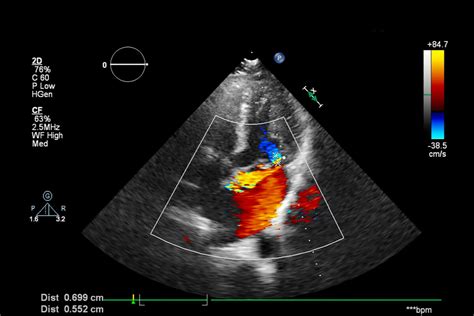

Il cuore di questa tecnologia diagnostica risiede nel principio fisico dell’effetto Doppler. Questo fenomeno, noto sin dal XIX secolo, descrive la variazione di frequenza di un'onda quando la sorgente o l'osservatore sono in movimento. In ambito ostetrico, questo principio viene applicato in modo ingegnoso: il Doppler ostetrico consente di misurare la variazione di frequenza delle onde ultrasonore riflesse dai globuli rossi in movimento. Questo significa che un fascio di ultrasuoni, una volta inviato, incontrerà i globuli rossi che si spostano nei vasi fetali. A causa del movimento di queste cellule, intercetterà una frequenza di ritorno differente rispetto a quella inviata. La variazione così percepita sarà quindi analizzata dal computer dell’ecografo, convertendo questi dati in informazioni visive e quantitative sul flusso sanguigno.

Questa tecnologia permette di analizzare in tempo reale il flusso ematico nei vasi sanguigni materni e fetali, fornendo informazioni che vanno oltre la semplice morfologia, e che riguardano la funzionalità e il benessere del feto. A differenza delle ecografie standard che si concentrano sulla struttura e sull'anatomia, il Doppler si addentra nella fisiologia, permettendo di capire come il sangue circola e se gli organi stanno ricevendo l'ossigeno e i nutrienti di cui hanno bisogno. L'esame si effettua mediante sonda ecografica transaddominale e non comporta alcun rischio né per la madre né per il bambino, rappresentando una procedura non invasiva e sicura. Attraverso l’analisi di questi dati, e l’incrocio con le principali tabelle utilizzate in ginecologia, è possibile arrivare a determinare una stima del peso fetale con buoni livelli di attendibilità, fornendo una panoramica completa sulla crescita e sullo stato di salute.

Il Doppler e il Flusso Sanguigno: Rivelare le Alterazioni Funzionali con il Significato dell'Eccentricità

L'ecografia Doppler, spesso inclusa nell'ecografia di accrescimento, riveste un ruolo di primaria importanza per la valutazione del flusso sanguigno nei vasi ombelicali e cerebrali del feto. Questo esame fornisce informazioni vitali sulla capacità della placenta di fornire ossigeno e nutrienti al bambino. Anomalie nel flusso sanguigno, che si manifestano con valori "elevati" o alterati degli indici di resistenza (come l'Indice di Pulsatilità - IP o l'Indice di Resistenza - IR), possono indicare una compromissione della funzione placentare e un rischio aumentato di sofferenza fetale. La flussimetria doppler è lo strumento migliore oggi a disposizione per la valutazione del benessere fetale e che costituisce la guida fondamentale per individuare il momento migliore per la nascita nei casi a rischio.

Flussimetria dei Vasi Fetali: Un Dettaglio Cruciale

Dalla 20^ settimana di gravidanza, durante l’indagine ecografica, si effettua anche la flussimetria dei vasi fetali. Questo esame permette di verificare in modo specifico la funzionalità vascolare del versante fetale della placenta e del cervello del feto. Le arterie ombelicali, che trasportano il sangue dal feto alla placenta, sono particolarmente importanti. Un flusso "elevato" in queste arterie, intendendo con ciò un aumento della resistenza al flusso (espressa dagli indici di resistenza o pulsatilità), indica che la placenta non sta funzionando in modo ottimale, rendendo più difficile il passaggio del sangue ricco di ossigeno e nutrienti.

Lo scopo della flussimetria è quello di individuare precocemente l’alterazione dei flussi sanguigni nel feto che può portare ad una carenza cronica di ossigeno ed a danni anche irreversibili. Le misurazioni più comuni in questo contesto includono:

- Flussimetria dell'arteria uterina: Valuta il flusso di sangue dalla madre all'utero e, di conseguenza, alla placenta. Un'elevata resistenza in queste arterie può suggerire un rischio di preeclampsia o IUGR.

- Flussimetria dell'arteria ombelicale: Misura la resistenza al flusso sanguigno attraverso la placenta. Valori "elevati" (alta resistenza o, nei casi più gravi, flusso diastolico assente o invertito) sono indicatori chiave di insufficienza placentare.

- Flussimetria dell'arteria cerebrale media: Valuta il flusso di sangue al cervello fetale. In caso di sofferenza fetale e ipossia, il feto tende a ridistribuire il sangue, aumentando l'afflusso al cervello per proteggerlo, fenomeno noto come "brain sparing" o "centralizzazione del circolo".